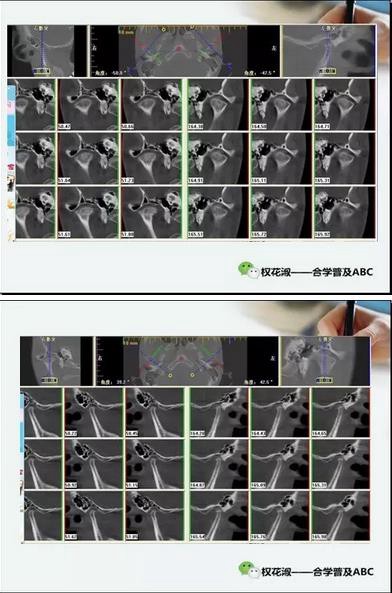

這是冠狀向和矢狀向的CT截圖,給大家一個粗略的概念,尤其是在看這個矢狀向的圖片,他們看他的關節(jié)已經非常纖細單薄,髁突的髁頭已經完全吸收了。回頭再看他第一張圖片,左側是一個口內前牙的開合,右側是一個CT側面的截圖,從這個截圖當中,大家可以進一步琢磨他下頜骨體的高陡,前后面高的變化,這些都提示我們他髁突已經有明顯的吸收。